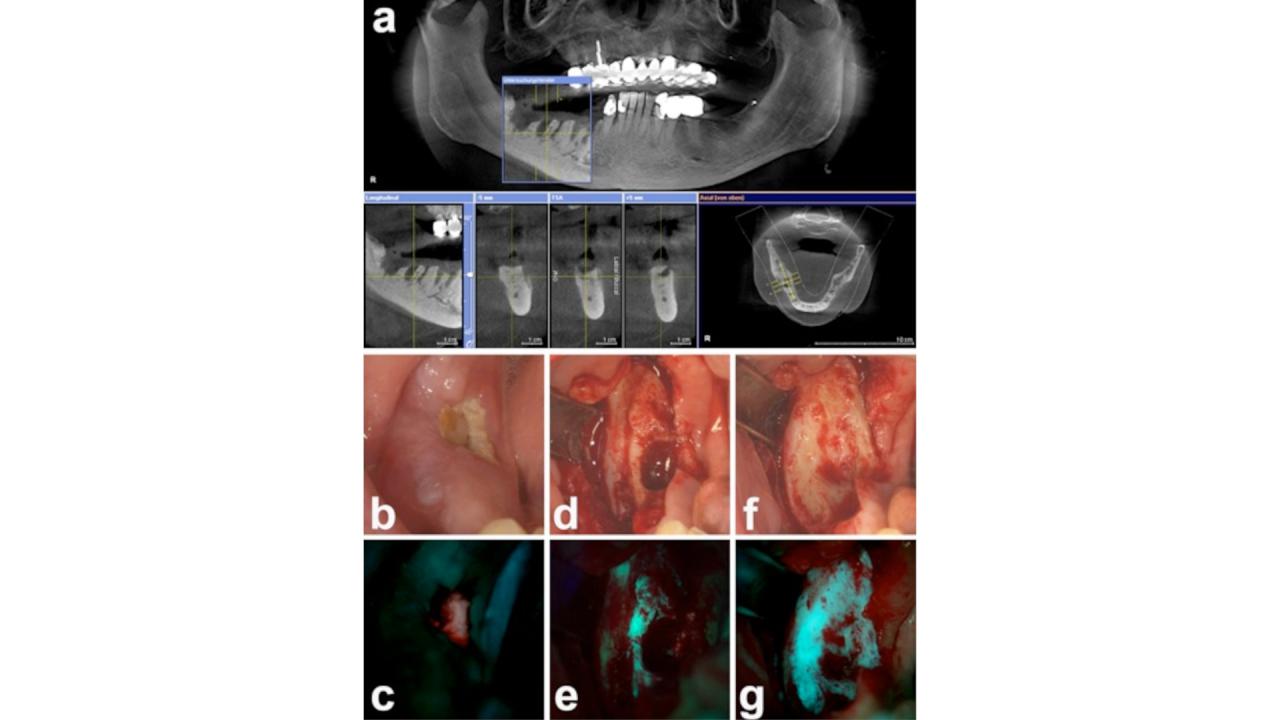

Die Fluoreszenzmarkierung von Knochen kann auch makroskopisch genutzt werden, um vitales von avitalem Knochengewebe zu unterscheiden und so möglicherweise chirurgische Therpieverfahren zu verbessern.

In vivo tetracycline labeling of bone – a helpful intraoperative parameter for the surgical therapy of osteoradionecrosis of the mandible